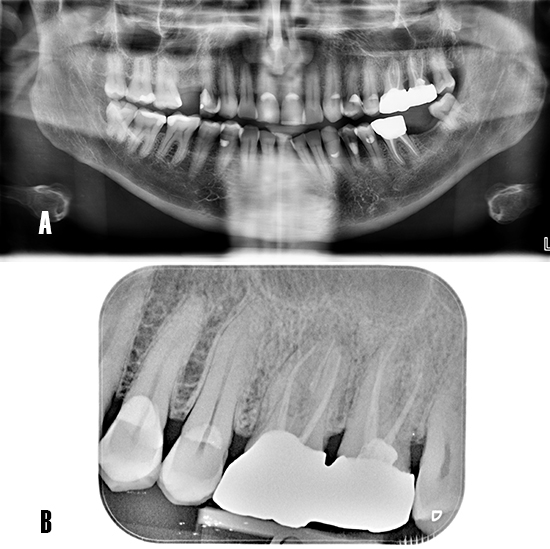

Tras realizar la evaluación radiológica bidimensional, en la ortopantomografía se observa los dientes 2.6 y 2.7 endodonciados y ferulizados mediante prótesis fija cementada (Fig. 2A). La radiografía periapical no evidencia una radiotransparencia bien definida a nivel apical. Las crestas alveolares interproximales se observan íntegras con bordes corticalizados bien definidos (Fig. 2B).

Figura 2. Evaluación radiológica bidimensional. A) La ortopantomografía advierte el tratamiento de conductos a nivel 26 y 27, portadores de prótesis fija metal-cerámica. B) La radiografía periapical muestra los dientes 26 y 27 endodonciados, se observa una imagen radiotransparente poco definida en apical de 26.

La TCHC muestra una imagen osteolítica menos radiodensa que afecta la región apical de 2.6, esta lesión compatible con un proceso osteolítico, es visible en los planos axial, coronal y sagital. Además, se observa cómo el seno maxilar izquierdo, relacionado al diente afectado, se torna más radiodenso y totalmente ocupado (Fig. 3).

Figura 3. Tomografía de haz cónico. A) Corte en el plano axial: se puede observar un área poco radiodensa en la raíz palatina de 26, y advierte la presencia de un proceso osteolítico de origen endodóntico. B) Corte coronal: se observa cómo el patrón de la lesión se extiende en sentido vestíbulo-palatino, además, se aprecia la cavidad sinusal anexa al diente afecto muy radiodensa respecto a su par contralateral. D) Corte sagital: se aprecia la opacificación completa del seno maxilar, la presencia de una septo óseo. La lesión apical tiene una mayor dimensión en la raíz palatina de 26.